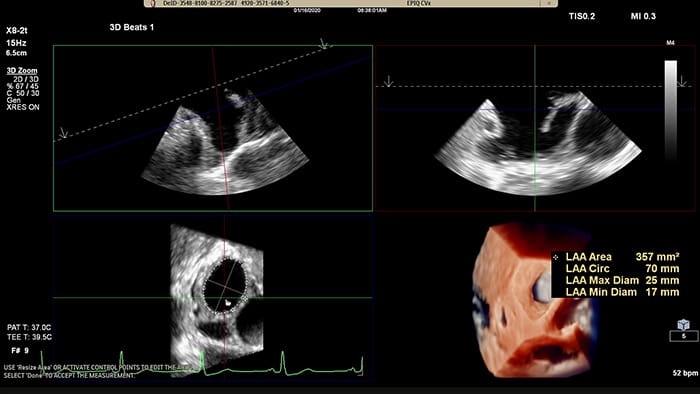

Rapidly acquire LAA orifice measurements in both traditional rendering or in TrueVue Glass rendering, with 3D Auto LAA